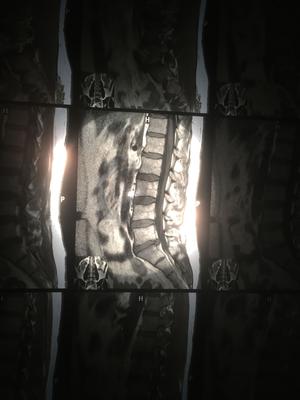

My back is crooked having at times great back spasms that last 1/2hr of pure hell. Pain does not go down legs but they are always tingly. I have Mri and Ct scans showing protrusions in both L4 L5 discs.

True, it doesn't look good. The MRI shows more than a protrusion; it's prolapsed. That in itself does not mean it's time for surgery though. This view of the scan only shows the problem at one level.